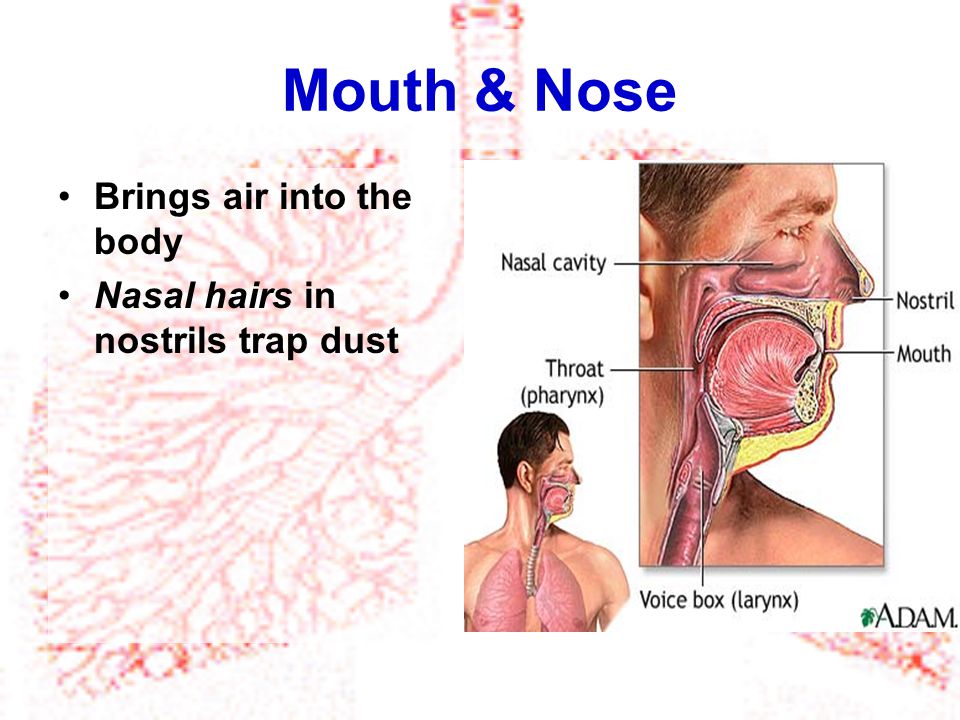

(1) Nostrils:

Air enters the body through the nostrils which are lined with a membrane of cells that secrets mucus which moistens the air we breathe.

(1) Nostrils:

Air enters the body through the nostrils which are lined with a membrane of cells that secrets mucus which moistens the air we breathe.